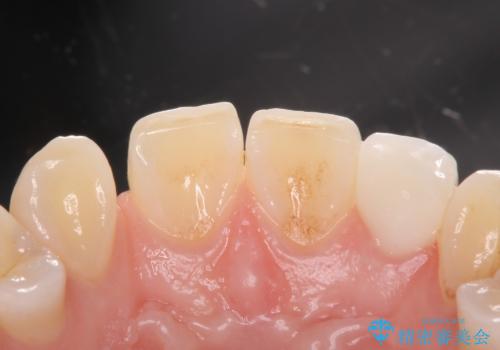

変色した前歯をキレイにしたい ジルコニアクラウンでの修復

- 左上の前歯の変色が気になるとのことで来院されました。

もともと小さい歯(矮小歯)に樹脂が盛り足されている状態でした。

- 左上2:仮歯+ジルコニアクラウン/11,000円+110,000円費用は治療当時の料金となります

セラミックでの治療をすることにより今後の変色を抑えることができます。

色・形ともに改善することができ大変喜んでいただけました。